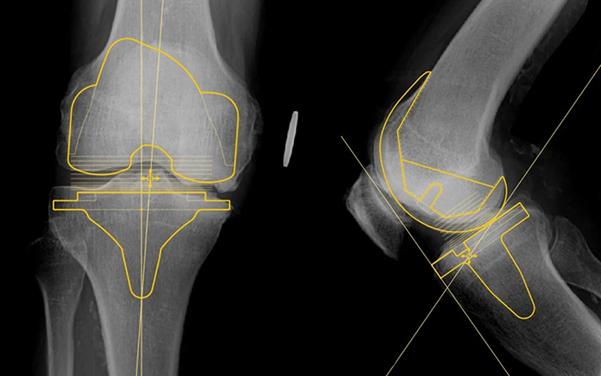

Lập kế hoạch tiền phẫu với Orthoview từ Materialise

Trong phẫu thuật chỉnh hình, kế hoạch tiền phẫu chính xác là yếu tố then chốt của thành công. Orthoview của Materialise không chỉ là phần mềm lập kế hoạch mà còn là giải pháp hỗ trợ bác sĩ chủ động và an toàn hơn trong từng quyết định. Đây là công cụ giúp chuẩn hóa quy trình phẫu thuật, đồng thời mở ra một cách tiếp cận mới - nơi công nghệ hiện đại cộng hưởng cùng kinh nghiệm lâm sàng và sự an toàn của bệnh nhân luôn được đặt lên hàng đầu.

Orthoview kết hợp công nghệ và chuyên môn, giúp bác sĩ tự tin hơn trước mỗi ca phẫu thuật

Điểm nổi bật:

- Lập kế hoạch toàn diện cho thay khớp, phẫu thuật cột sống và kết hợp xương.

- Đo đạc trực tiếp trên X-quang để lựa chọn implant chính xác và tối ưu.

- Tích hợp liền mạch với hệ thống PACS, thao tác thuận tiện trên dữ liệu hình ảnh sẵn có.

- Thư viện implant toàn cầu, liên tục cập nhật, giúp bác sĩ tiếp cận nhiều giải pháp trên một nền tảng duy nhất.

- Một license duy nhất cho phép truy cập toàn bộ ứng dụng và thư viện của Materialise.

Orthoview từ Materialise (Bỉ): Lập kế hoạch tiền phẫu toàn diện, nâng cao độ chính xác lâm sàng

Phần mềm hỗ trợ bác sĩ chủ động trong từng quyết định phẫu thuật, chuẩn hóa quy trình và tối ưu lựa chọn implant dựa trên dữ liệu hình ảnh thực tế.